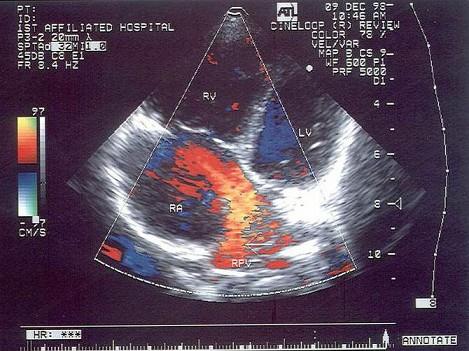

该病例最有可能诊断是?(?)A.原发孔房缺B.继发孔房缺C.冠状静脉窦隔缺损  D.部分性肺静脉畸形引流E.部分型心内膜垫缺损

选项 A.原发孔房缺 B.继发孔房缺 C.冠状静脉窦隔缺损   D.部分性肺静脉畸形引流 E.部分型心内膜垫缺损

答案 D